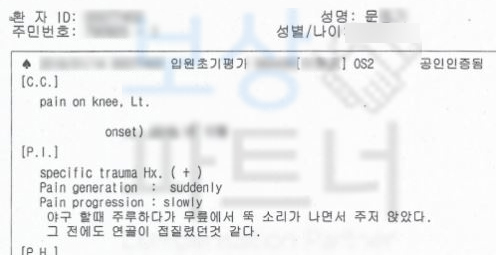

문@@님은 운동을 즐기시던 중 무릎의 갑작스러운 소리와 함께 통증을 호소하셨습니다.

위 초진 기록지를 보시면 왼쪽 무릎의 통증을 호소하신 것과 사고 경위가 대략적으로 언급되어 있습니다. 이 사고로 받은 진단은..!

전방십자인대 파열 좌측 s8352